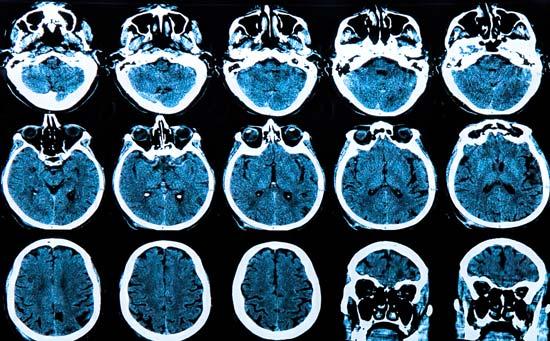

Demencia: ¿Qué causa la pérdida de memoria de mi madre?

Demencia

Distinguir entre los tipos de demencia

Para los médicos y las familias empeñados en lograr un diagnóstico, un factor de complicación importante es la existencia de muchos tipos de demencia. Más de 50 condiciones pueden imitar o causar demencia.

Con el tiempo las células cerebrales mueren, provocando la pérdida de tejido. En estudios por imágenes, la contracción del cerebro generalmente en el hipocampo es donde primero se detecta, región que juega un papel central en la memoria.